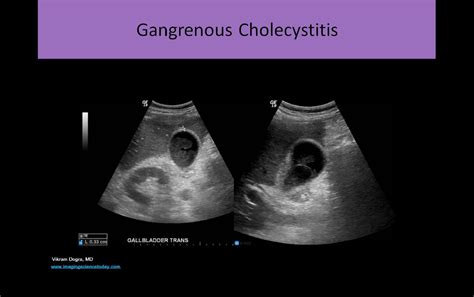

• Liver and Gallbladder Issues: Evaluating the size, shape, and structure of the liver and gallbladder to detect conditions such as gallstones, liver disease, and tumors.

After the ultrasound of the abdomen is completed, the images are reviewed by a radiologist who specializes in interpreting ultrasound results. The radiologist will look for any abnormalities or signs of disease in the abdominal organs and provide a detailed report to the referring physician. The results of the ultrasound can help guide further diagnostic tests or treatment plans.

It is important to note that while an ultrasound of the abdomen is a valuable diagnostic tool, it may not always provide a definitive diagnosis. In some cases, additional imaging tests such as CT scans or MRIs may be recommended to obtain more detailed information.